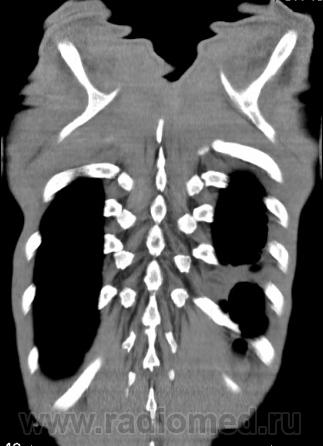

На фоне консолидации полость без содержимого. Может быть всё что угодно, что сопровождается деструкцией. Нужны ещё томограммы в лёгочном окне.

Туберкулёз.

Туберкулёз?

Это КТ 2-летней давности и попало оно мне в руки, после недавнего прохождения контроля пациентом, когда мы стали перед вопросом о специфическом / не специфическом процессе.

Тогда, пациента 2 месяца лечили от пневмонии, лечили интенсивности, стационарно, в серьёзном учреждении.

Предположу аспергиллез